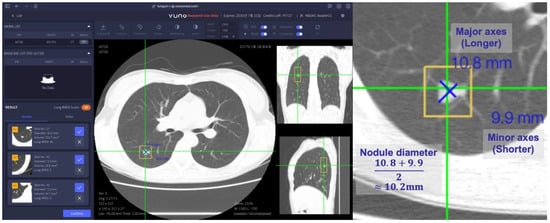

2.1.4. Computer-Aided Detection